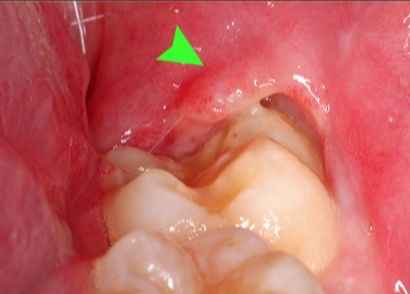

这种情况可能得了「智齿冠周炎」

牙冠周围软组织的炎症

临床上多见下颌第三磨牙(俗称智齿)

智齿是牙列中最后萌出的牙,因萌出位置不足,可导致程度不同的阻生。阻生智齿或萌出过程中的智齿牙冠可能被龈瓣覆盖,形成盲袋,成为食物残渣、渗出物及细菌的场所,当抵抗力下降、局部细菌浸入时可引起急性冠周炎。特别是孕宝妈在怀孕期间体内激素水平及生活作息变化或致抵抗力下降,更容易发生智齿冠周炎如果炎症得不至有效的控制容易影响胎儿发育。